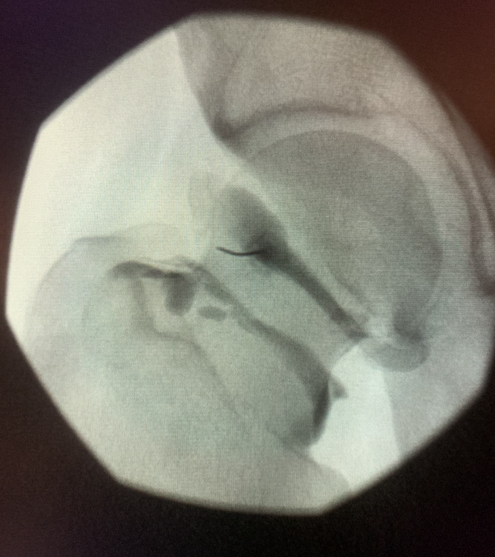

Musculoskeletal Imaging

Arthrography of any joint

There are many reasons your doctor may want Musculoskeletal Imaging. These include investigating the causes of joint and bone pain and conditions such as arthritis, tendon and ligament tears, meniscal tears, fractures, bone tumors and bone or joint infections.